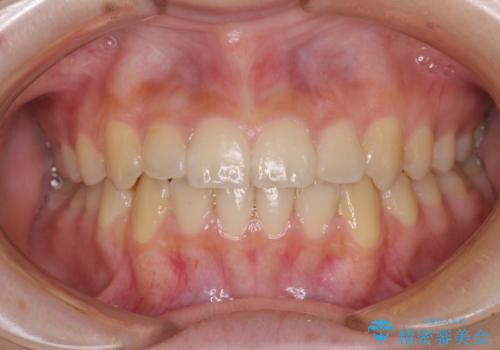

歯並びのがたつきを直したい ワイヤーは嫌 抜きたくない